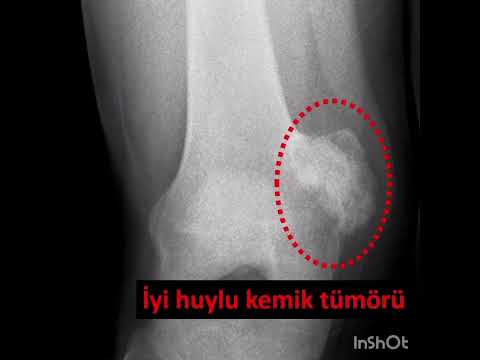

Tıbbi olarak vücutta oluşan her tür şişliğe tümör denir. Bunun içinde malign yani kötü huylu tümörler olabileceği gibi benign yani iyi huylu tümörler de yer alır. Metastaz dediğimiz iç organ kanserlerinin kemiklere yayılması da tümördür.

Kemik tümörlerinin tanısında basit röntgenler çok önem taşır ve doğru şekilde değerlendirildiğinde yeterli olabilir. Ancak kötü huylu olabileceği düşünülen ya da yumuşak doku tümörlerinde mutlaka MR çekilmelidir. MR kontrastlı olmalı ve yeterli kalitede olacak şekilde çekilmelidir. Aksi halde hasta tekrar MR çektirmek zorundadır. Kemik tümörlerinde zaman zaman bilgisayarlı tomografiden de yararlanılır. Ayrıca kemik taraması isteniyorsa, ya da tümörün diğer kemiklere yayılıp yayılmadığının anlaşılabilmesi için kemik sintigrafisi de önem taşır. PET ise son derece özel bir görüntüleme yöntemi olup henüz tanı almamış hastalar için yeri yoktur.